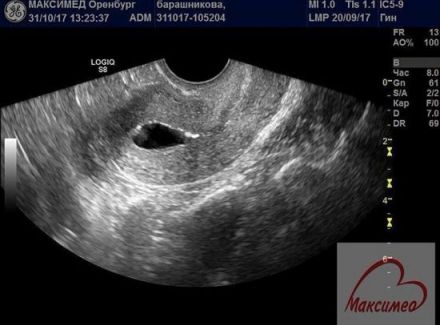

Наиболее безболезненным и безопасным методом

диагностики проходимости является Эхогистеросальпингоскопия ( ЭХОГСС).

Процедура проводится двумя специалистами: гинекологом и врачом ультразвуковой

диагностики.

Женщине вводится через тонкий катетер в полость матки

небольшое количество стерильной жидкости. При этом врач с помощью ультразвука

оценивает поступление раствора через маточные трубы в брюшную полость или его

не поступление. ЭХОГСС показывает врачу не только проходимость, но и другие

факторы, влияющие на возможность забеременеть: локализацию спаек, контур, форму

и толщину труб, миомы и полипы, аномалии развития матки: наличие перегородки

или ее удвоение; особенности формы, сращения (синехии). На основании УЗ-картины

врач выдает заключение и рекомендации.